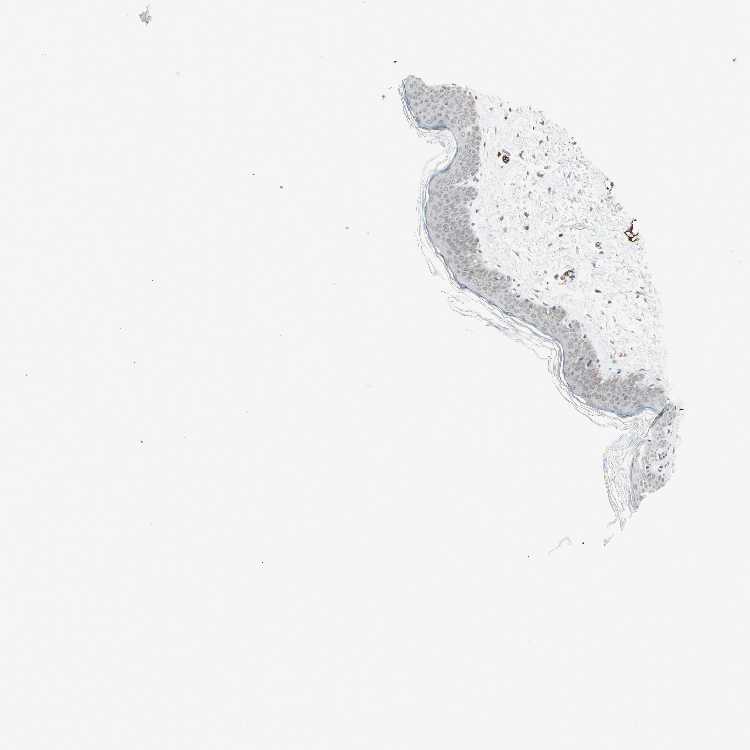

SKIN 1 - Antibody stainingi

Antibody staining in the annotated cell types in the current human tissue is reported as not detected, low, medium, or high, based on conventional immunohistochemistry profiling in selected tissues. This score is based on the combination of the staining intensity and fraction of stained cells.

Each image is clickable and will lead to virtual microscopy that enables deeper exploration of all samples and also displays staining intensity scores, fraction scores and subcellular localization as well as patient and tissue information for each sample.

Antibody HPA010570

Langerhans Not detected

Fibroblasts Not detected

Keratinocytes Low

Melanocytes Low